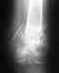

Здравствуйте! 31 августа 2010 г. попал в ДТП (мотоциклист). В итоге оскольчатый перелом н/3 со смещением обеих костей голени. Гематомы, некроз кожи в обл. перелома, жировая эмболия. Также были сломаны медиальный мыщелок, и межмыщелковое возвышение б/берцовой кости (на данный момент сросшиеся). Что касается голени, то результат виден на снимке - прошло 6,5 месяцев после травмы, и 4,5 месяца после операции (аппарат Илизарова).

А теперь по порядку: при поступлении получил скелетное вытяжение, пробыл на нем около 2-х месяцев. За это время меня лечили от эмболии; делали репозицию; дренировали гематому в месте перелома (сначала разрезали скальпелем и вытащили основную часть гематомы, далее дренажные трубки); после созревания некроза (3х10 см) произведена некрэктомия, далее ждали грануляцию, потом аутопластика раны кожным лоскутом; после того как лоскут прижился была произведена операция (спустя 2 месяца с момента получения травмы) - чрезкостный остеосинтез методом Г.А.Илизарова. Сейчас прошло 4,5 месяца после операции - б/берцовая кость не сраслась, м/берцовая - тем более, даже не попадает отломками. Мужики, что делать? Мне 24 года, я люблю активный образ жизни и не хочу становиться калекой. Врач, который меня оперировал каждый раз говорит, что всё сростется и отправляет гулять ещё на 1,5 месяца. А с аппаратом Илизарова особо не погуляешь. Раньше ходил на костылях, теперь хожу с тросточкой с полной нагрузкой на травмированую ногу. Я понимаю, что нужно время, НО! за 4,5 ммесяца должна же образоваться костная мозоль, хоть какие-то признаки сращивания? А м/берцовая кость, что с ней делать (врач обещал, что непременно срастется - ошибся?!). Уважаемые врачи, специалисты, вы моя последняя надежда - жду ваших советов по поводу/методике дальнейшего лечения, а также прогнозов. Стоит ли ждать сращивания и ходить в аппарате, либо готовиться к операции и ставить интрамедуллярный штифт? С, уважением, Олег Иванов.